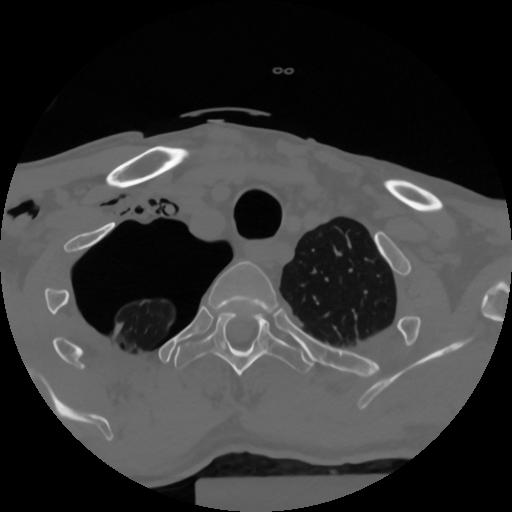

12 P.BLANDAS,,Vol,0.5,P.BLANDAS,,